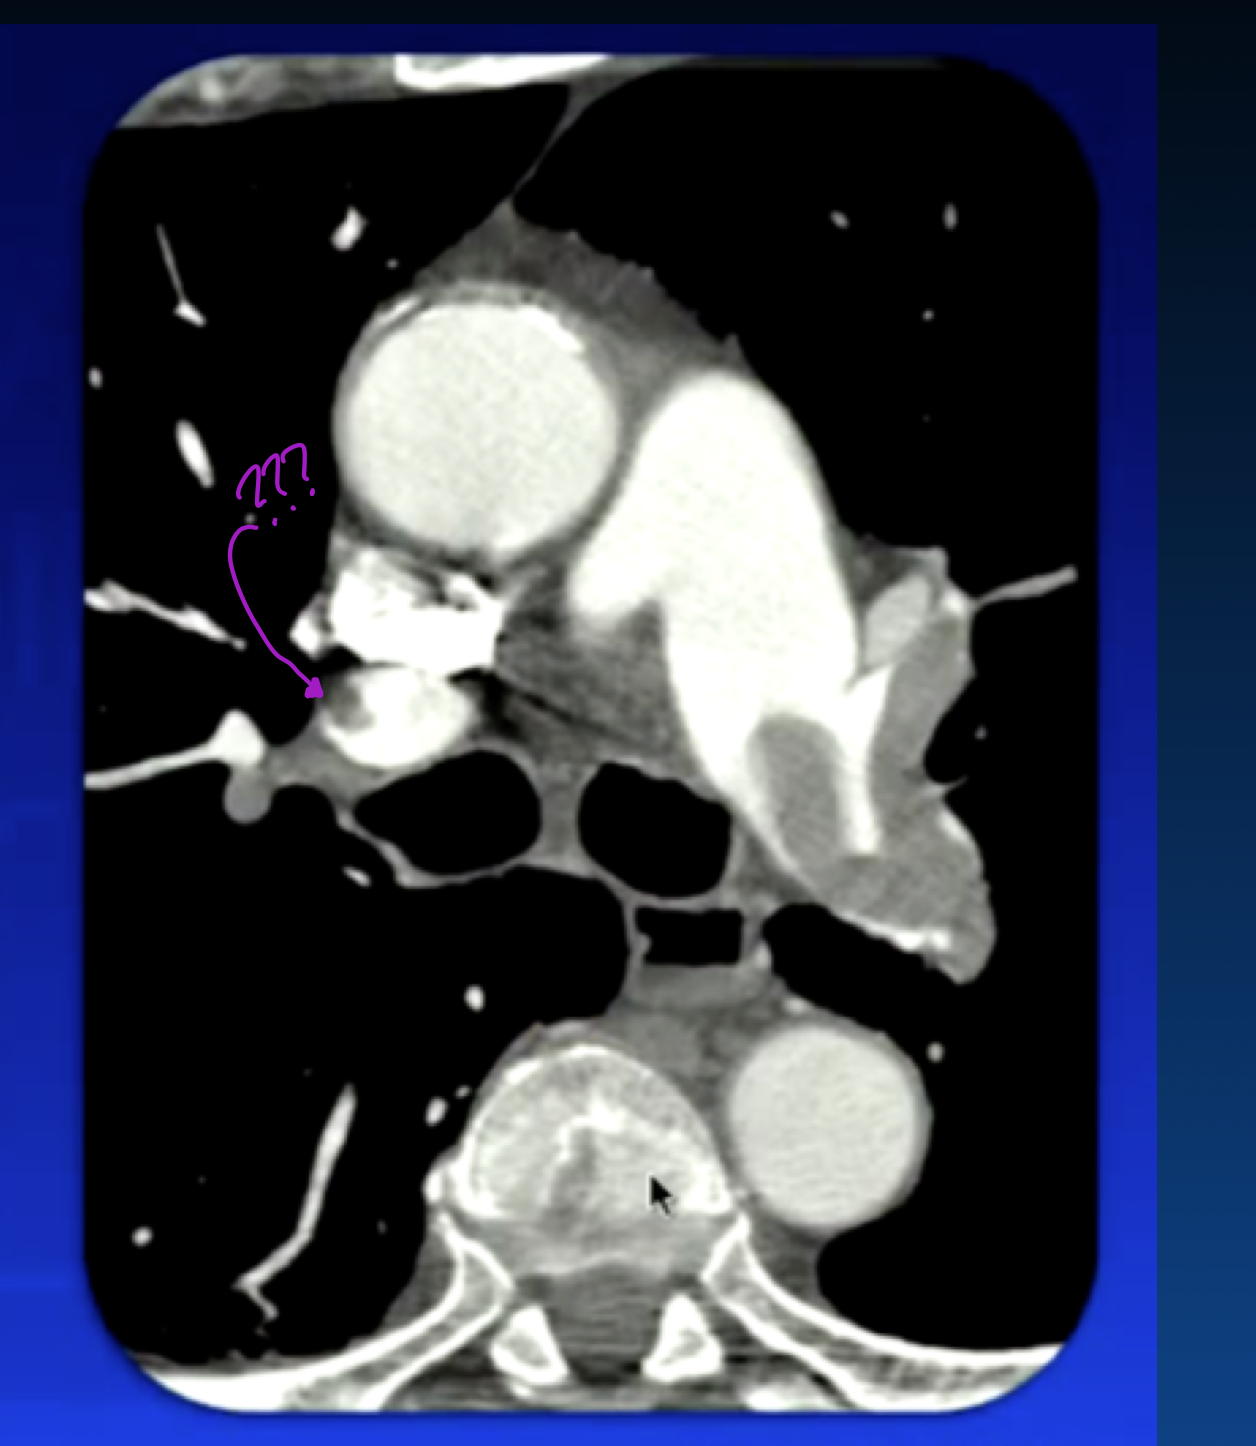

Saddle Embolism: When it goes over bifurcation of pulmonary artery

eccentric clot